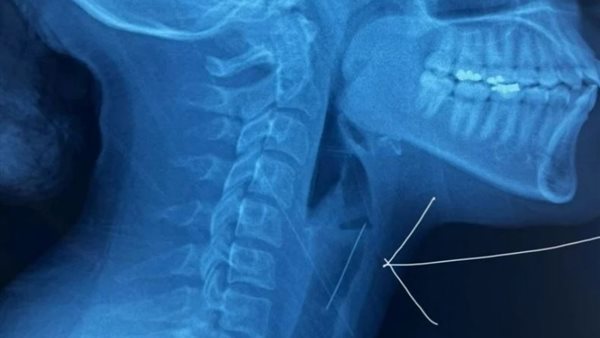

ووفقًا لتقارير إعلامية، وصلت الشابة إلى المستشفى في حالة طارئة بعدما علِق الدبوس في حنجرتها، مما استدعى تدخلًا طبيًا عاجلًا، وكشفت الفحوصات الطبية والأشعة المقطعية أن الدبوس استقر في منطقة حساسة، مما تطلب إجراءً جراحيًا دقيقًا.

وبفضل فريق طبي متخصص، تم استخدام منظار حنجري متطور مزود بكاميرا دقيقة، مما ساعد في استخراج الدبوس بأمان دون التسبب في أي أضرار للحلق أو القصبة الهوائية.